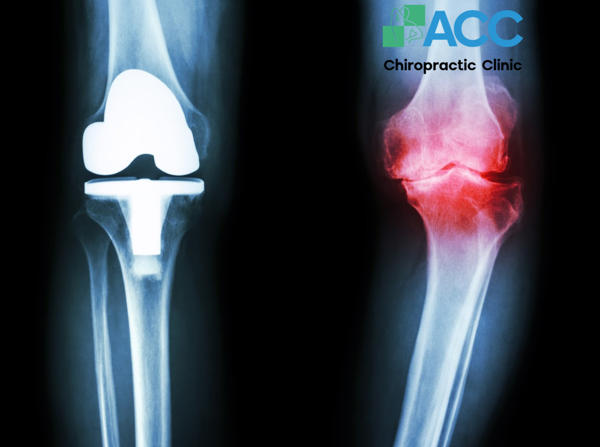

1.9. Viêm khớp

Viêm khớp cũng là một loại chấn thương đầu gối khá phổ biến, làm cho khớp và vùng xung quanh khớp bị sưng lên vô cùng khó chịu. Lúc này, người bệnh không chỉ đau mà còn phải đối mặt với tình trạng cứng khớp, chuyển động bị hạn chế và đôi khi có cảm giác lạo xạo bên trong khớp gối khi cử động. Bên cạnh yếu tố di truyền, chấn thương cũng có thể góp phần gây viêm xương khớp.

Dấu hiệu nhận biết: Một số dấu hiệu thường gặp của viêm khớp gồm đầu gối ấm nóng khi ấn vào, cứng khớp vào buổi sáng sớm hoặc sau khi ngủ trưa (kéo dài khoảng 10 – 30 phút) và phát ra tiếng lụp cụp, răng rắc khi gập duỗi đầu gối.